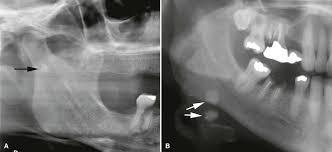

What may an untreated Ranula become?

Plunging Ranula

Dissects through the mylohyoid muscle

May cause death –> closes of esophagus and airway

Sialolith (Sialolithiasis)

Calcifications developed in salivary duct

** SUBMANDIBULAR gland – long duct **